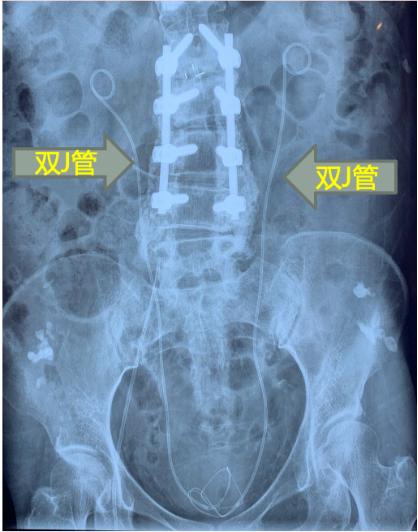

要说这高级抗生素真是给力:李阿婆的血压和体温很快恢复到了正常,也不恶心呕吐肚子痛了,复查的各项指标也明显好转。由于存在肾结石、输尿管结石、肾积水,李阿婆被转到了医院的泌尿外科,做了输尿管结石的激光碎石。为了防止术后输尿管水肿或损伤引起再次梗阻,医生按照常规,在她的输尿管里装上了支架——双J管,让“下水道”排水通畅,等术后过一段时间输尿管长好了再拔掉;而肾结石医生则建议待后续再行处理。

潘教授一一翻阅了检验报告,发现了问题所在:白色念珠菌。这种真菌虽然不是普通人群中常见的尿路感染病原体,但是李阿婆也不属于“普通人群”——她的尿路中有植入的双J管。

在人体天然的尿路上,白色念珠菌难以粘附,即使偶然有白色念珠菌进入尿路,也会被尿液冲刷出体外,这种情况下尿液培养出“白色念珠菌”确实有污染所致的嫌疑;然而在外来的“异物”双J管上,白色念珠菌可以轻松粘附进而感染。而且李阿婆有四次尿培养阳性,白色念珠菌所致的尿路感染“实锤”了,一定需要进行针对性治疗。

革命尚未成功,因为李阿婆的身体里的感染源头没有解决:作为外来的“异物”,双J管上容易被白色念珠菌粘附,长时间感染之后,他们早已在双J管上安家落户,形成了坚韧的堡垒——生物膜,药物无法渗透,只有把这个管子拔掉,才可能彻底解决问题。但李阿婆的拔管时机未到,如果此时拔管,李阿婆的输尿管可能会出现狭窄甚至闭塞,后果不堪设想。而且李阿婆身体里还存在着未处理的肾结石,他们的表面也会有病原体黏附、也是持续感染的源头。

最终,经过联合讨论与充分的术前准备,泌尿外科医生给李阿婆同时进行了尿管扩张、钬激光碎石取石和双J管置换术,处理了结石的同时更换了新的双J管。拔出来的管子上附着着成片的白色絮状物,其中检出了大量的白色念珠菌;取出来的结石也检出了大量的白色念珠菌:他们就是李阿婆顽固尿路感染的“养蛊密室”、“万恶之源”。